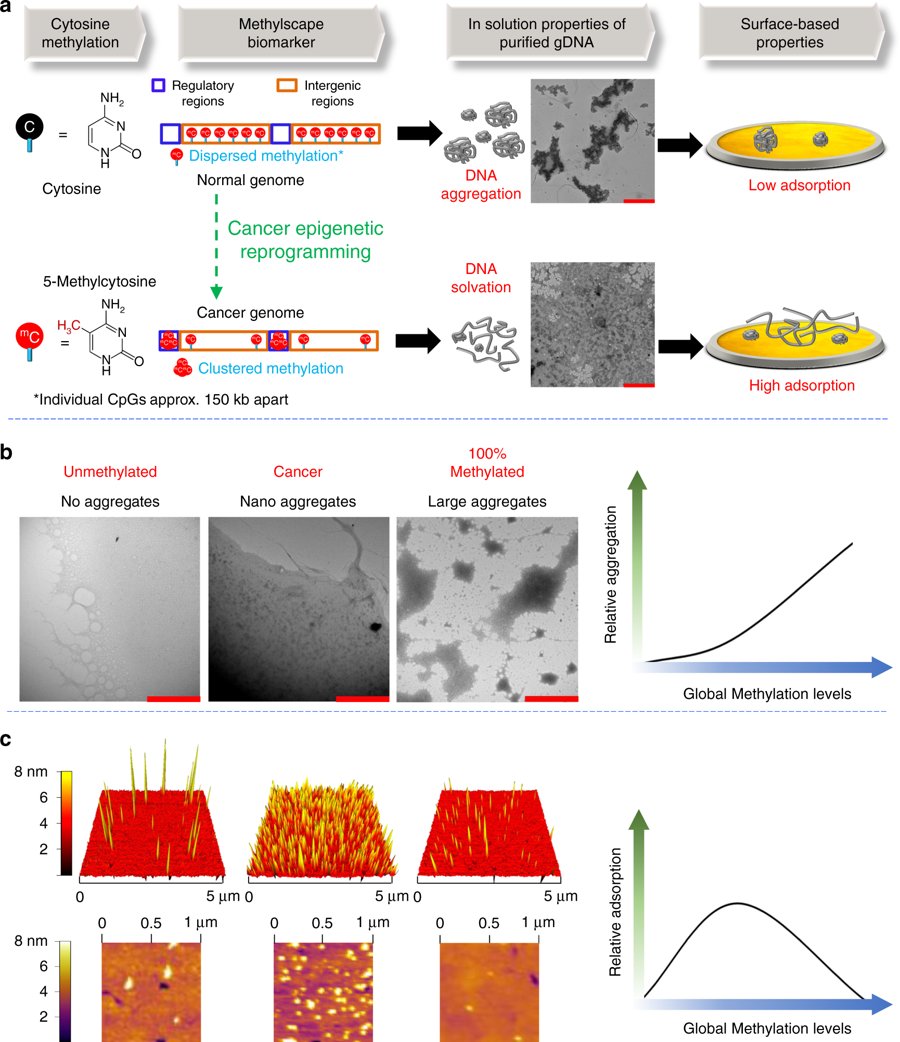

Fundamental differences between cancerous and normal genomes have led to the 'Methylscape' - a universal biomarker displayed by most cancers. This allows for an analysis time of <10 minutes to detect many cancer types. Read the full paper in

@NatureComms: https://buff.ly/2St4puY pic.twitter.com/VUAvHBivDH ಧನ್ಯವಾದಗಳು. Twitter ಇದನ್ನು ನಿಮ್ಮ ಕಾಲರೇಖೆಯನ್ನು ಉತ್ತಮಗೊಳಿಸಲು ಬಳಸುತ್ತದೆ. ರದ್ದುಗೊಳಿಸುರದ್ದುಗೊಳಿಸು